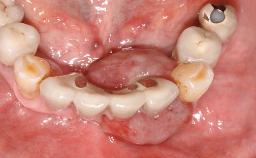

The case concludes with the presentation of the final prostheses at the 3-year follow-up, demonstrating a stable and pleasing soft- and hard-tissue situation.